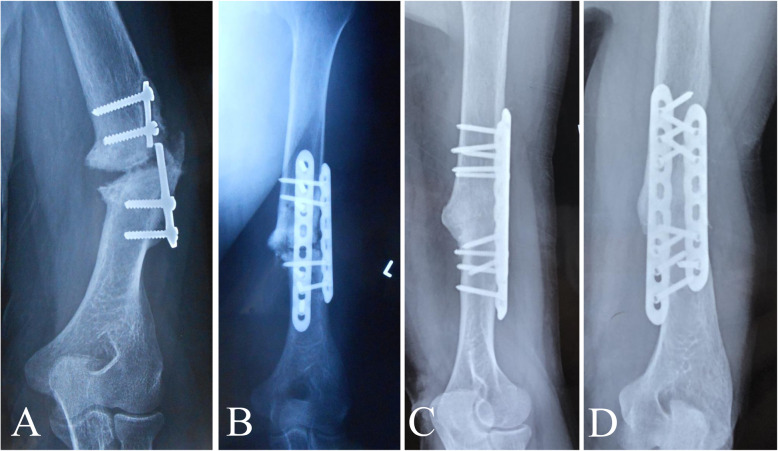

Images from a 58-year-old man who underwent plate fixation of a left humerus shaft fracture 30 years ago and was treated with plate fixation combined with autogenous iliac crest bone grafting because of nonunion 1 year postoperatively. However, the humeral fracture remained un-united until he visited our institution. a Preoperative plain radiograph showing classic synovial pseudarthrosis nonunion of the left humerus with a broken plate. b Radiograph taken immediately after revision surgery showing double locking compression plating with autogenous iliac crest bone grafting. c, d Radiographs showing consolidated bone union at 45 months after the index surgery